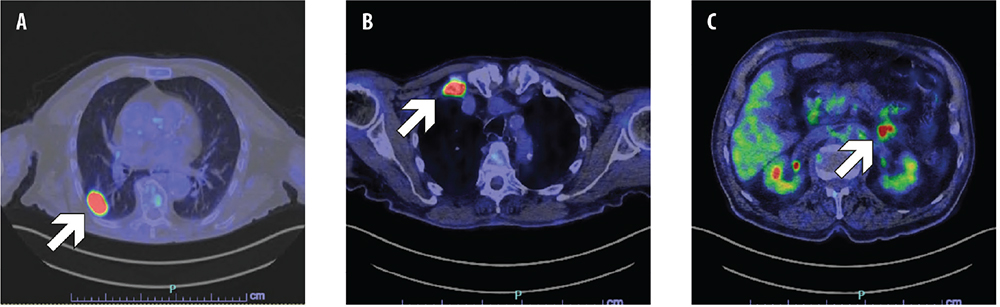

Following an accidental fall, a former 86-year-old male smoker underwent a head and chest computed tomography (CT) scan, which showed a lung tumor in the right lower lobe. The 18F-fluorodeoxyglucose (FDG) positron emission tomography (PET)/CT confirmed the presence of a lung tumor and showed bone, left adrenal and peritoneal metastases (Fig. ;1). Stage was cT1c N0 M1c, IVB according to the American Joint Committee on Cancer (AJCC) 8th edition. The pathology examination of a CT-guided biopsy of the lung mass diagnosed lung adenocarcinoma with sarcomatoid transformation. The immunohistochemical evaluation showed high PD-L1 expression with a tumor proportion score (TPS) ≥50%, and next-generation sequencing (NGS) found METex14 skipping mutation. Comorbidities included trigeminal neuralgia, prostatic hypertrophy, eye maculopathy, and bilateral knee and right hip replacement.

Fig. 1 - Positron emission tomography-computed tomography (PET-CT) scan showing primary lung tumor (A), bone metastasis in the first right rib (B), and peritoneal metastasis (C).